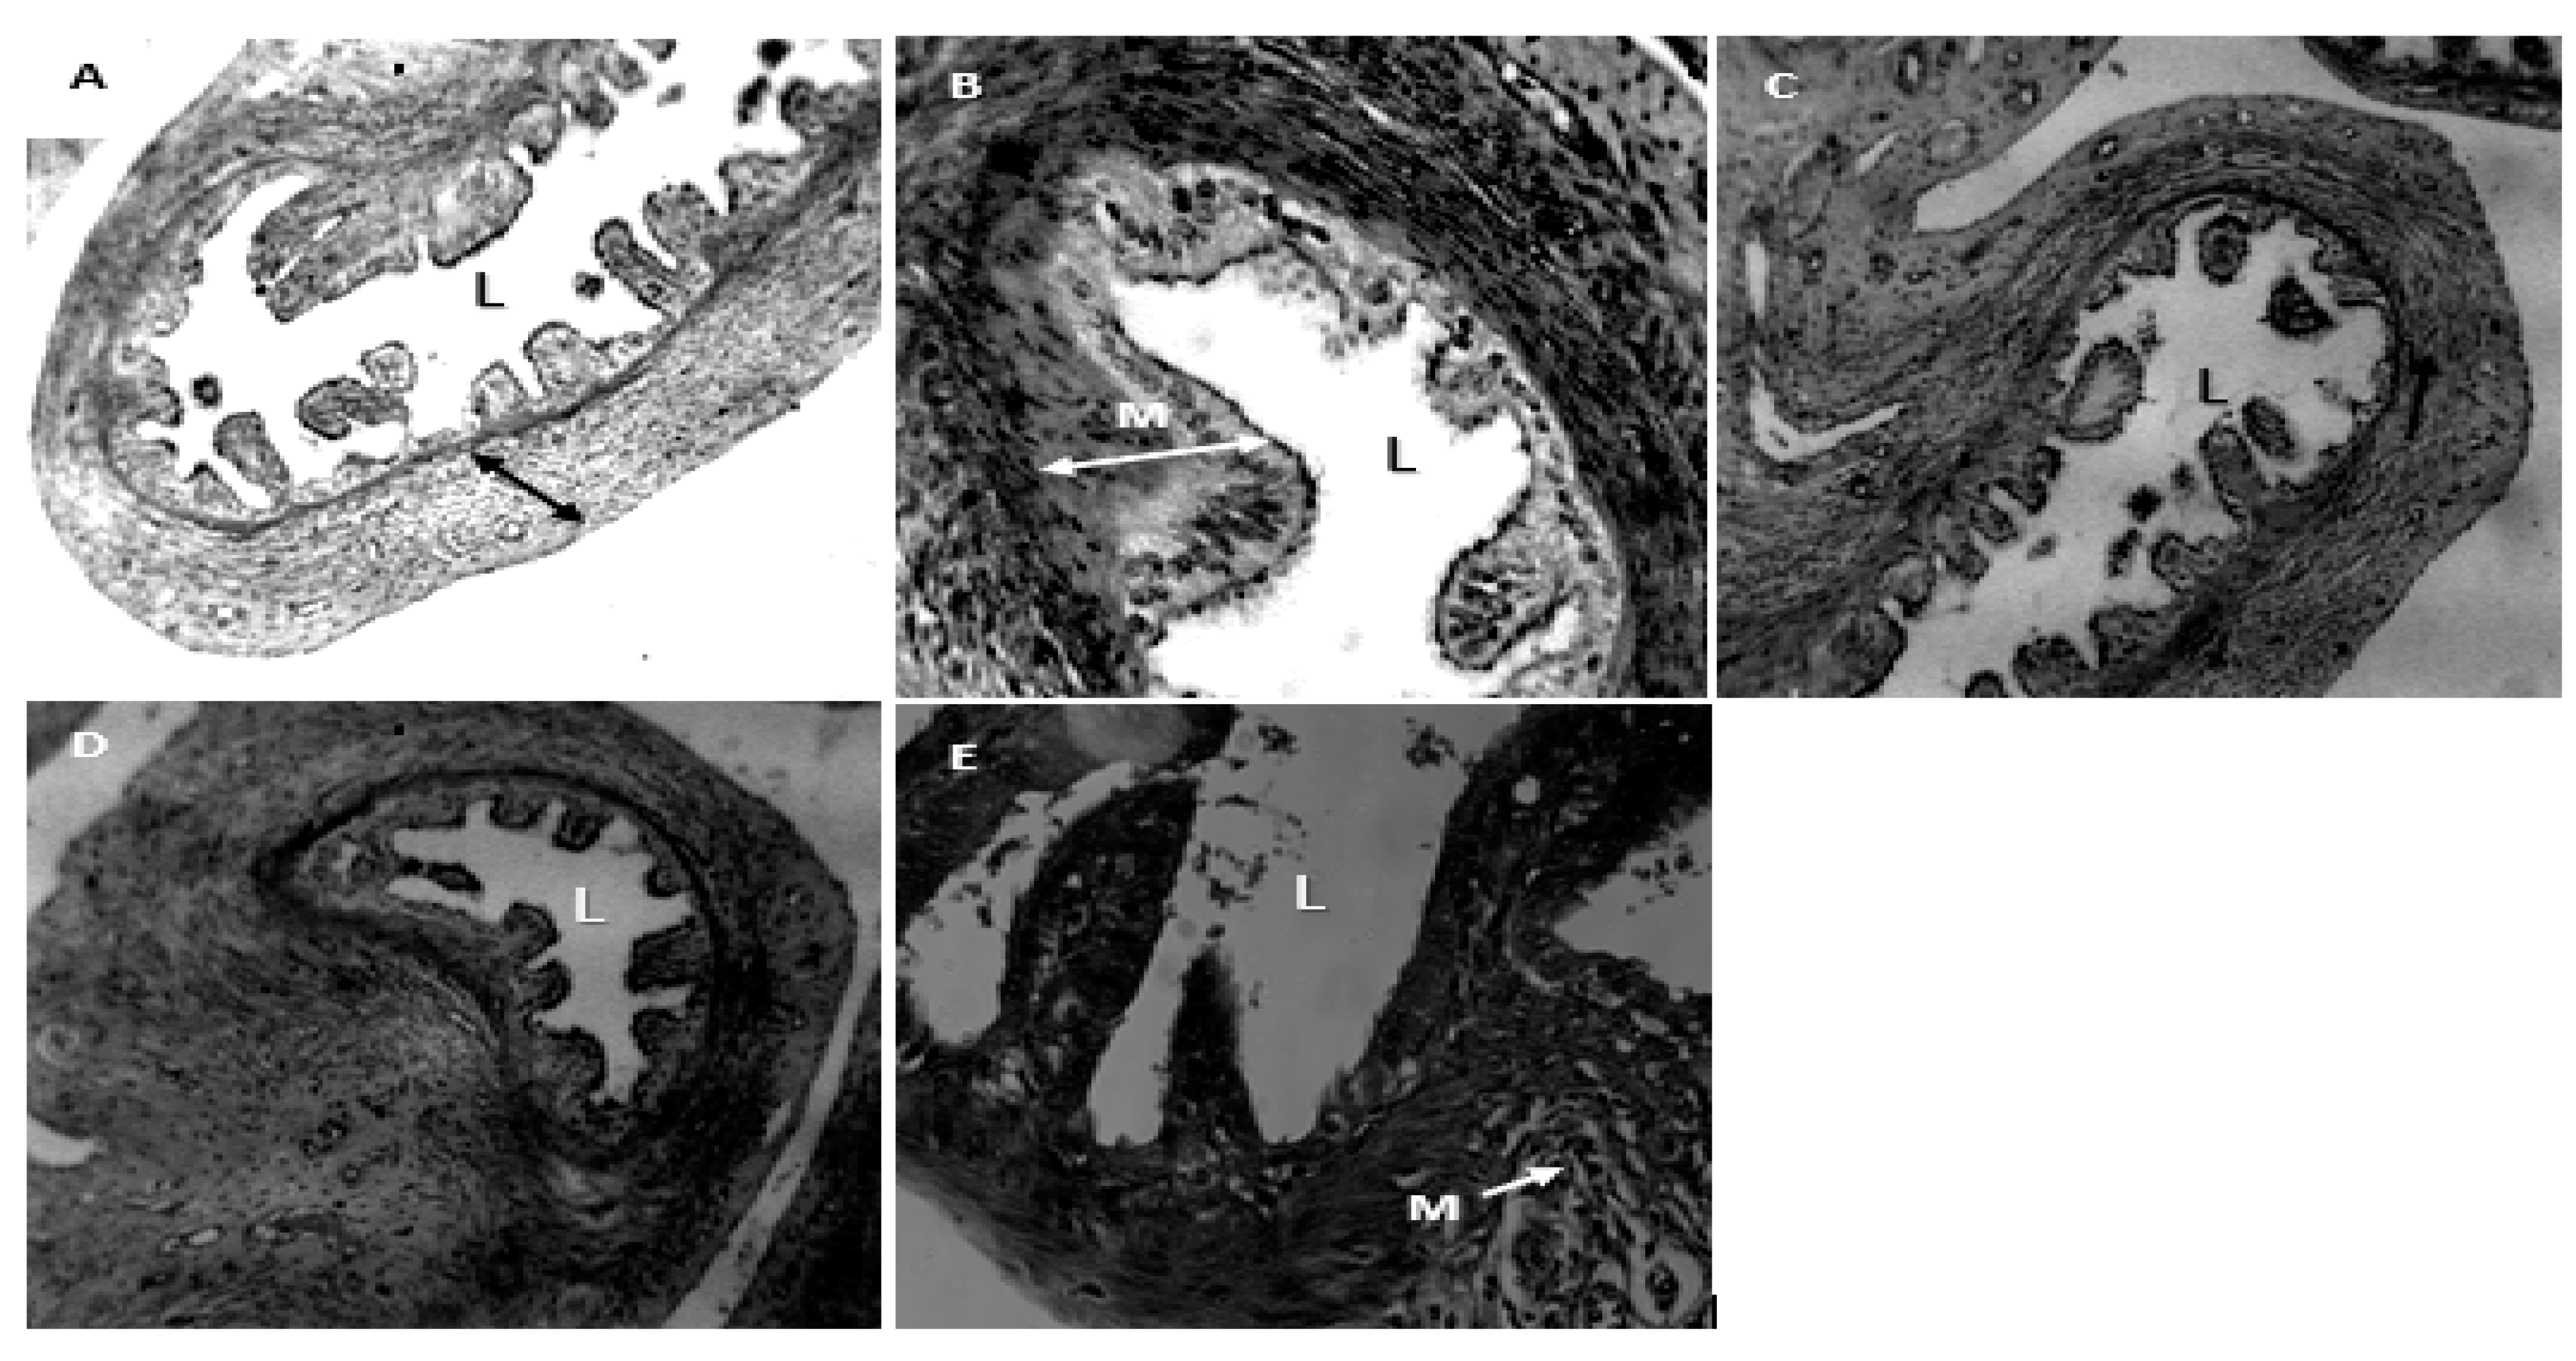

- A.

- Group 1 (Positive Control): Normal appearance of uterine mucous membrane with branching folds, and central lumen (L).

- B.

- Group 2. (Negative Control): Shows increased activity of the mucous membrane of the uterine tube

- C.

- Group 3. (200mg/kg NS-oil + 0.5mg/kg Cy), also shows decrease mucous activity, the muscularis mucosa also shows decrease in diameter

- D.

- Group 4. (400mg/kg NS-oil + 0.5mg/kg Cy), Narrowing of the luminal diameter can be seem in this group

- E.

- Group 5. (800mg/kg NS-oil + 0.5mg/kg Cy). The uterine tube is less intact and numerous distortions can be seen. There is also and increased proliferation of the mucous membrane